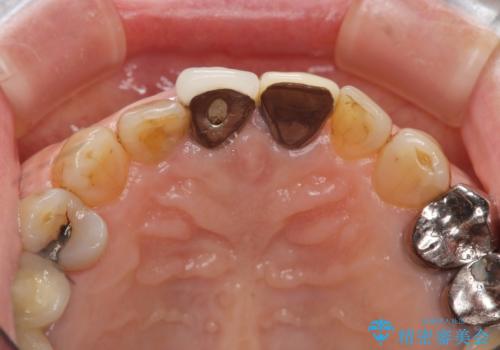

前歯の審美改善

- 孫娘の結婚式に合わせて前歯を綺麗にして写真映りをよくしたいと来院されました。

結婚式に合わせて根管治療からのやりかえを短期集中治療で計4回で終える計画を立てます。

- 40万円(仮歯・ファイバーコア・ジルコニアクラウン×3)費用は治療当時の料金となります